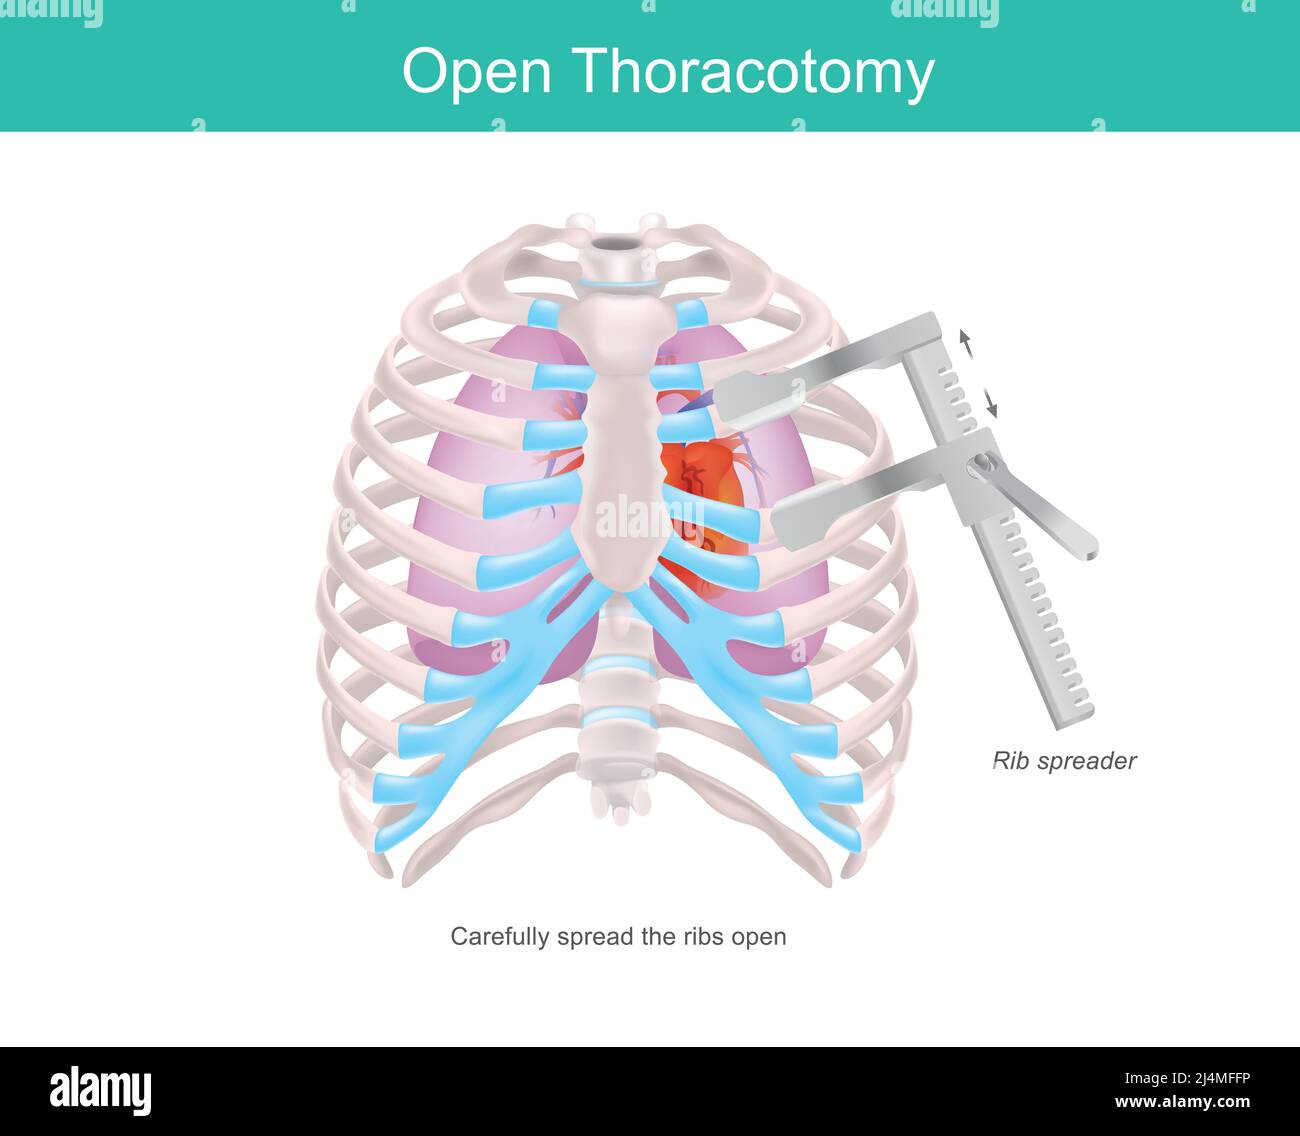

Toracotomia aperta. Una procedura per accedere allo spazio pleurico del torace umano mediante uno strumento medico chiamato Rib spreader. Illustrazione Vettorialehttps://www.alamy.it/image-license-details/?v=1https://www.alamy.it/toracotomia-aperta-una-procedura-per-accedere-allo-spazio-pleurico-del-torace-umano-mediante-uno-strumento-medico-chiamato-rib-spreader-image467589802.html

Toracotomia aperta. Una procedura per accedere allo spazio pleurico del torace umano mediante uno strumento medico chiamato Rib spreader. Illustrazione Vettorialehttps://www.alamy.it/image-license-details/?v=1https://www.alamy.it/toracotomia-aperta-una-procedura-per-accedere-allo-spazio-pleurico-del-torace-umano-mediante-uno-strumento-medico-chiamato-rib-spreader-image467589802.htmlRF2J4MFFP–Toracotomia aperta. Una procedura per accedere allo spazio pleurico del torace umano mediante uno strumento medico chiamato Rib spreader.